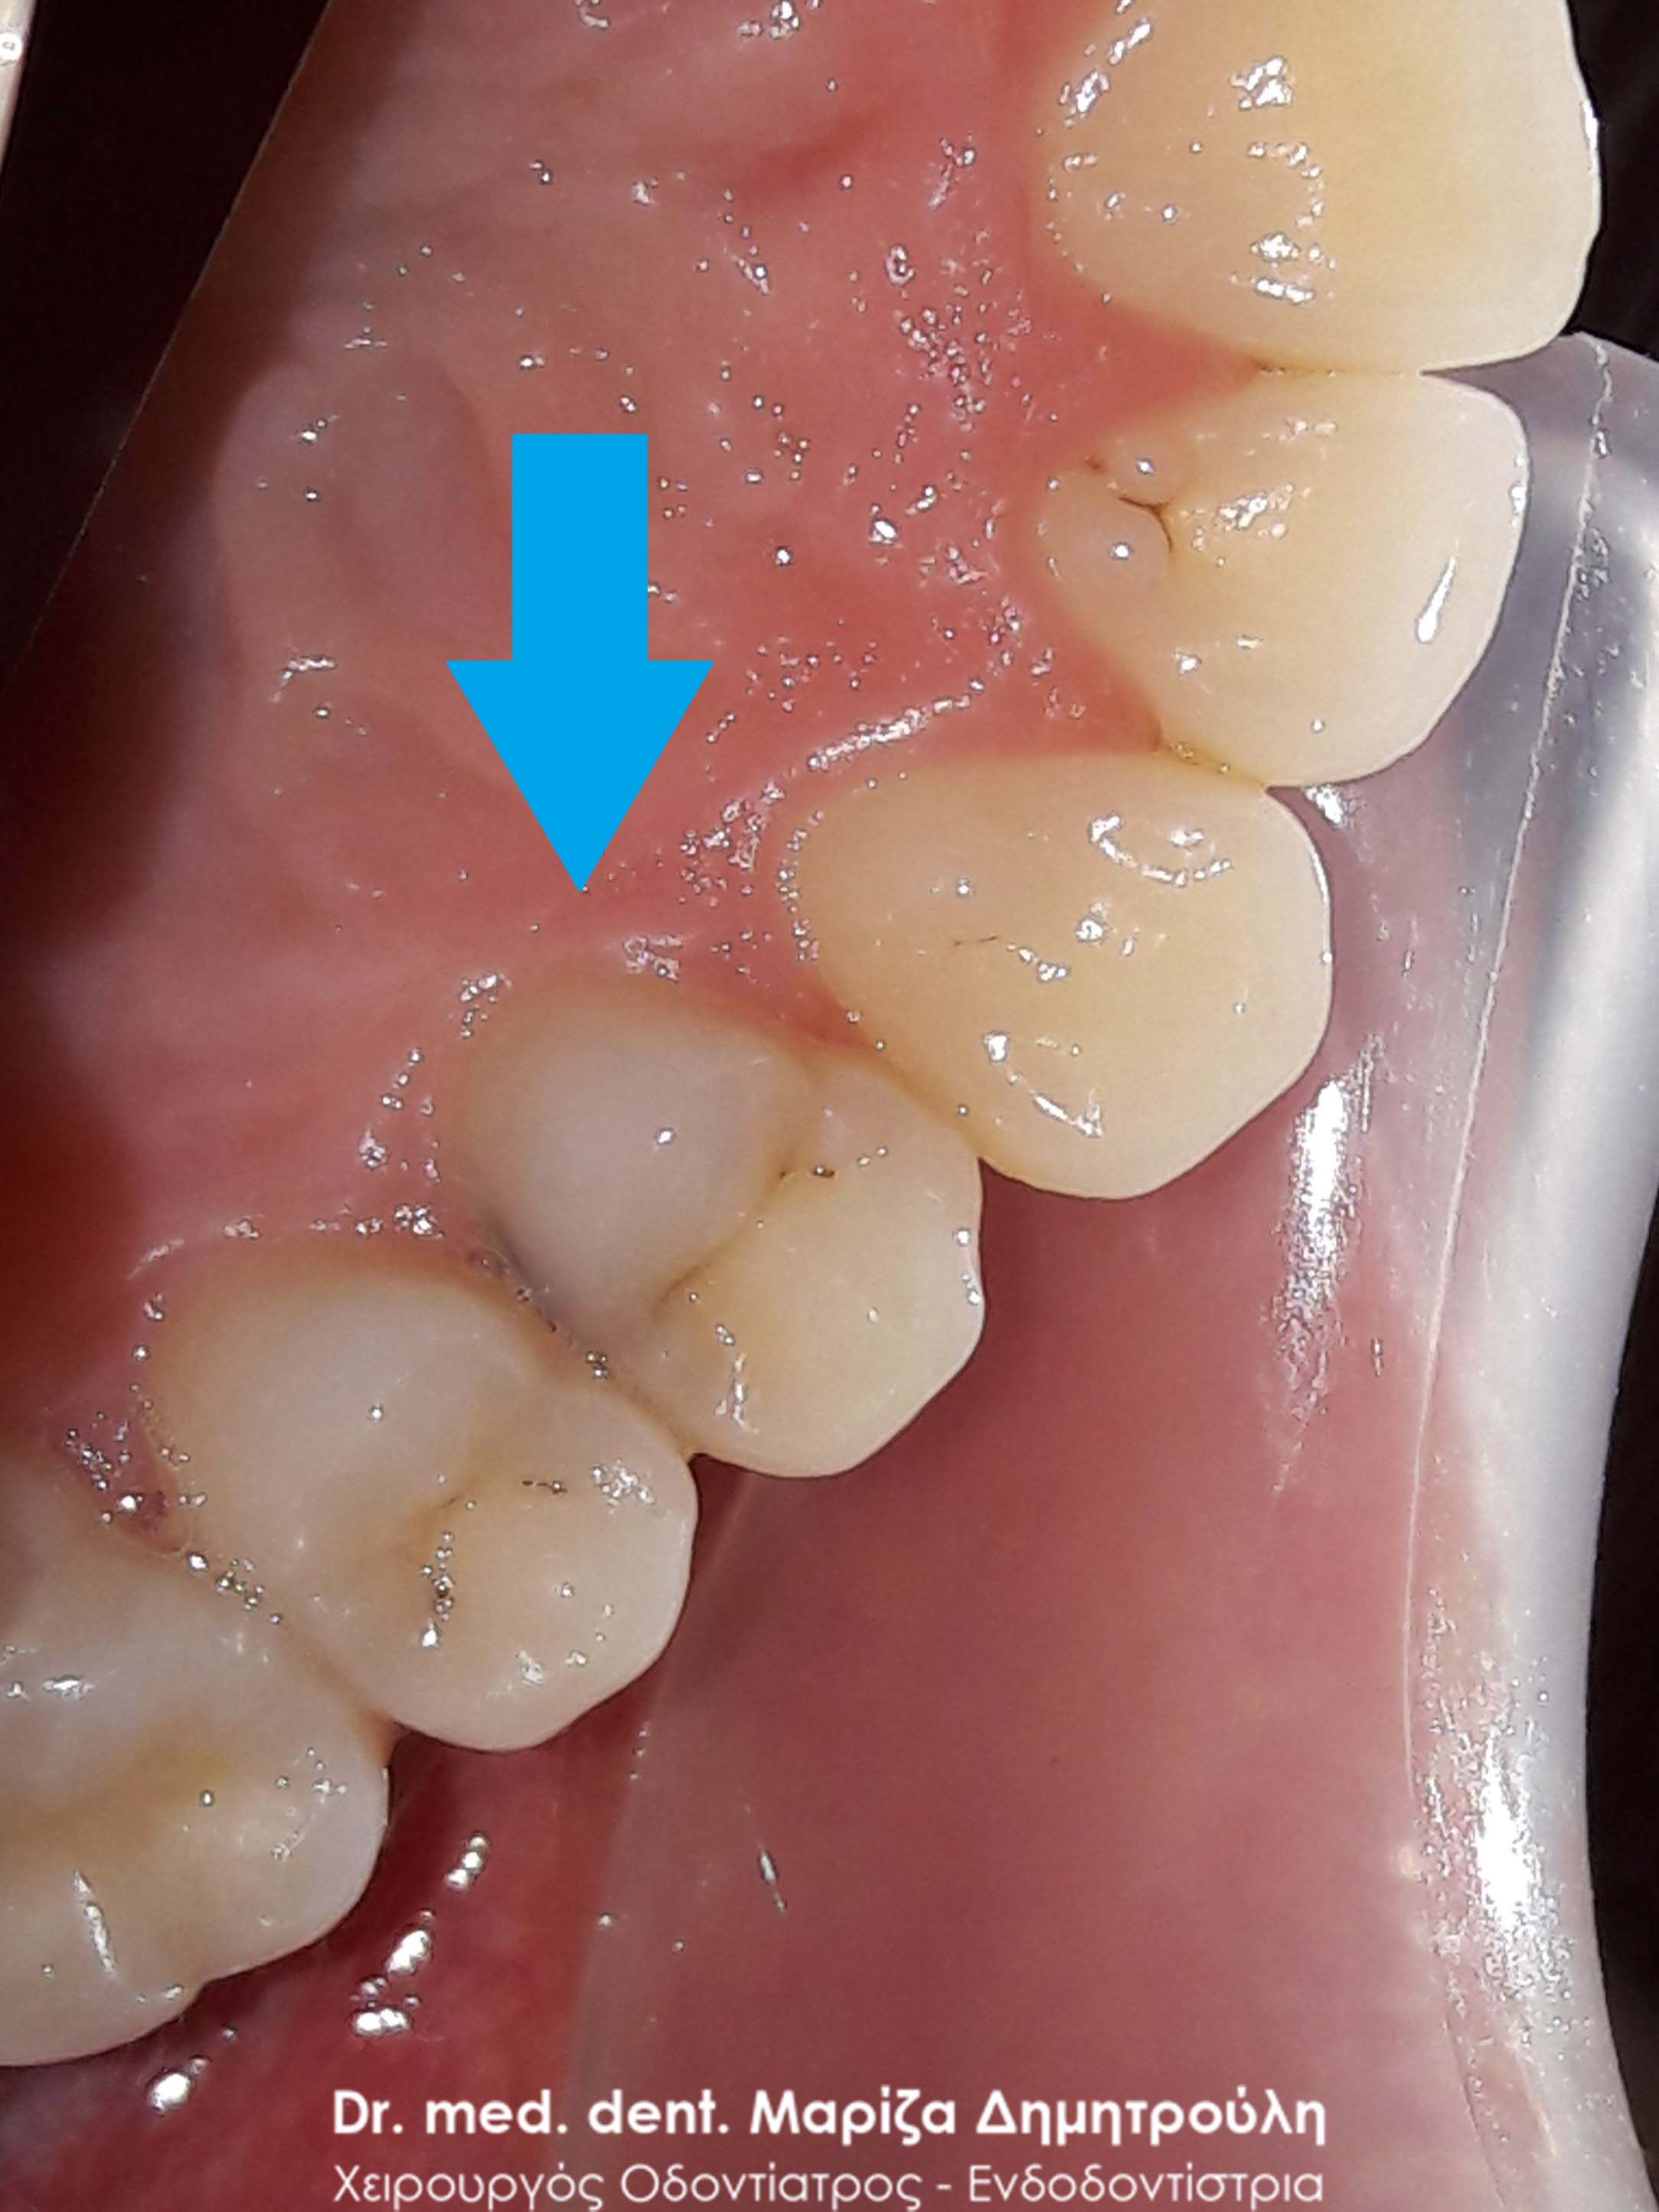

Περιστατικό – Λευκά σφραγίσματα δύο δοντιών

Στα πλαίσια του ετήσιου οδοντιατρικού ελέγχου εντοπίστηκαν στον ασθενή δύο μικρής έκτασης τερηδονισμένα δόντια στη δεξιά πλευρά της άνω γνάθου. Τα παλιά λευκά σφραγίσματα που διέθεταν οι δύο άνω δεξιοί γομφίοι είχαν επανατερηδονιστεί. Μετά τη χορήγηση τοπικής αναισθησίας αφαιρέθηκαν οι παλιές λευκές εμφράξεις των δοντιών, απομακρύνθηκε η τερηδόνα και να δόντια αποκαταστάθηκαν με νέα λευκά σφραγίσματα ρητίνης.

ΠΡΙΝ

META